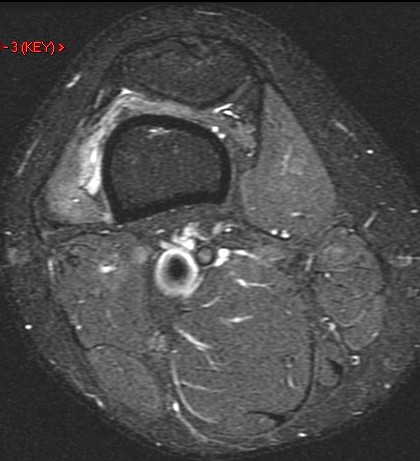

27 y/o patellar tendon rupture with repair 2 years ago. Re-injury 1 year ago. Now with increasing pain and limited range of motion.

Figure 1 for case Patellar tendon re-tear

Figure 1

The acute changes have resolved but the patient has a re-tear of the tendon. The patella is retracted superiorly. Important to measure the length of gap as well as any residual tendon for surgical planning.

Patellar tendon re-tear